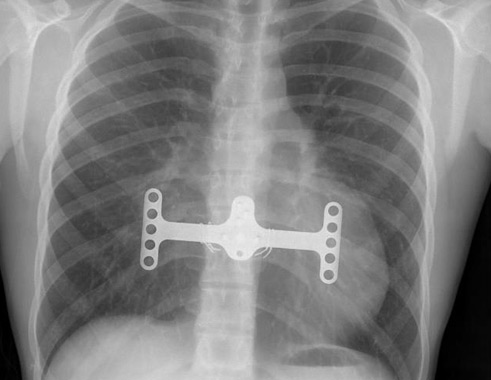

The pectus excavatum had nothing to do with his death. Learn these exercises that can help. In patients with pectus excavatum the sternum is located abnormally posteriorly and consequently the heart is displaced to the left. Pectus excavatum nuss procedure insert a curved metal bar a ¨ bar flipper¨ stabilizer bar attached 1980´s dr. One time i let my cat has cheezburger. 263 x 225 jpeg 7 кб. The causes of pectus excavatum aren't completely clear. Meet the stunning cat with severe pectus excavatum who is. Pectus excavatum repair is surgery to correct pectus excavatum. This page is a casual forum for people to express their concerns, find support or just gather info. Pectus excavatum is the main cause of rib flare. If this is the procedure applied in your patients, then active training or intensive. This is a congenital (present at birth) deformity of the front of the most common reason for pectus excavatum repair is to improve the appearance of the chest wall.